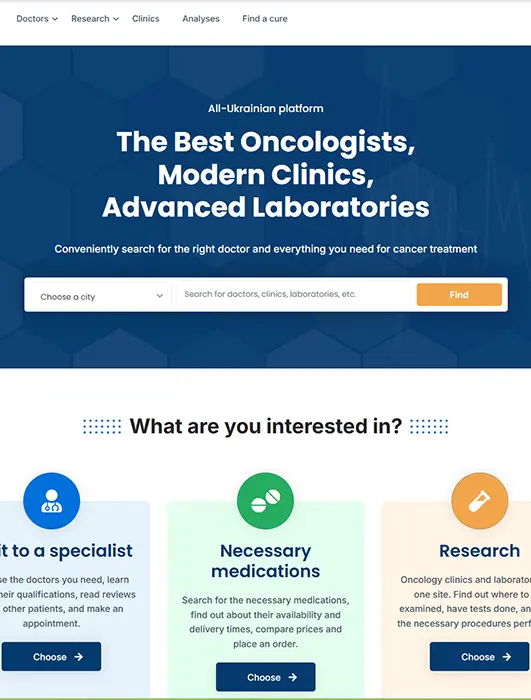

Build Powerful Digital Products

We design and develop high-quality software tailored to your business goals. From corporate websites and complex CRM systems to cloud platforms and mobile apps — our engineers create scalable, secure, and user-friendly solutions that drive efficiency and digital growth.